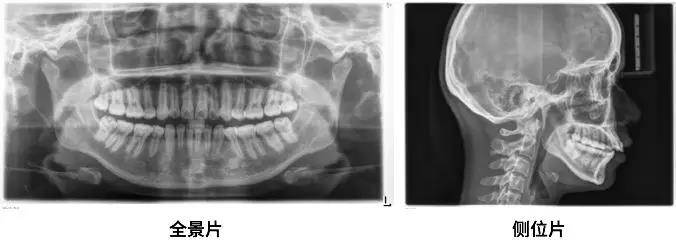

拍片

一般在面診時

醫師通常會讓你拍兩張X光片

一張全景一張側位

通過這兩張片子

醫師能夠對你的牙齒、牙根、牙槽骨、頜骨

甚至關節等進行判斷、數據分析

看到一些肉眼無法發現的問題

所以呢

一般至少要拍兩張片子

是必須的

如果不拍就直接給你結論

你反而要小心了哦